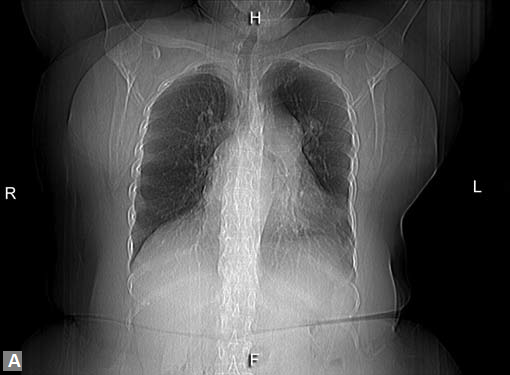

Unexplained breathlessness, patches of consolidation in

CXR, unexplained pleural effusion should be investigated

with CT angiogram to exclude the possibility of pulmonary

thromboembolism.